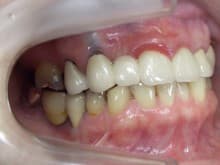

歯周病専門治療

歯周病専門治療 「腫れや出血が引き、安心!」

歯周病の症例をご紹介します。 側切歯間に審美補綴が入っています。 ご覧のように歯茎が真っ赤になってしまっているのもよくわかりますね。 歯茎は、一度腫れてしまうと、腫れが引いた時 少し下がってしまうこと…